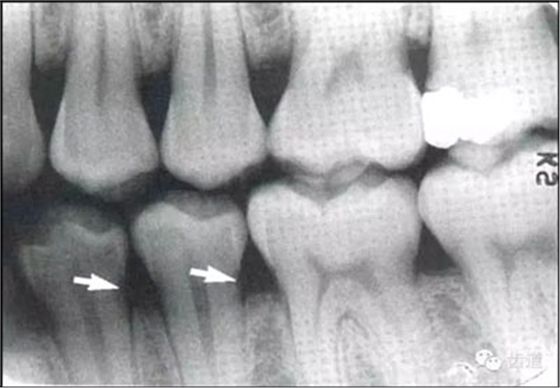

常見(jiàn)于下頜前牙區(qū),在牙根之間的牙槽骨內(nèi)并與牙長(zhǎng)軸平行的密度低的條狀影像。此為小血管進(jìn)入牙槽突的影像。